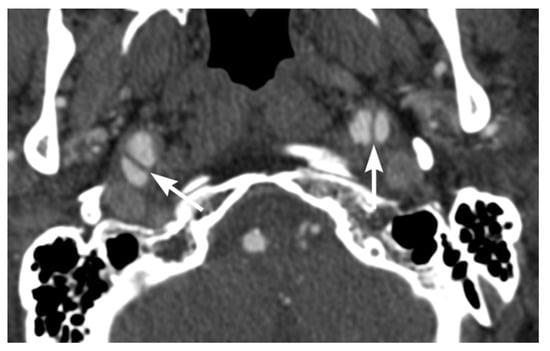

2. Imaging Techniques

3. Imaging Findings of Arterial Injury